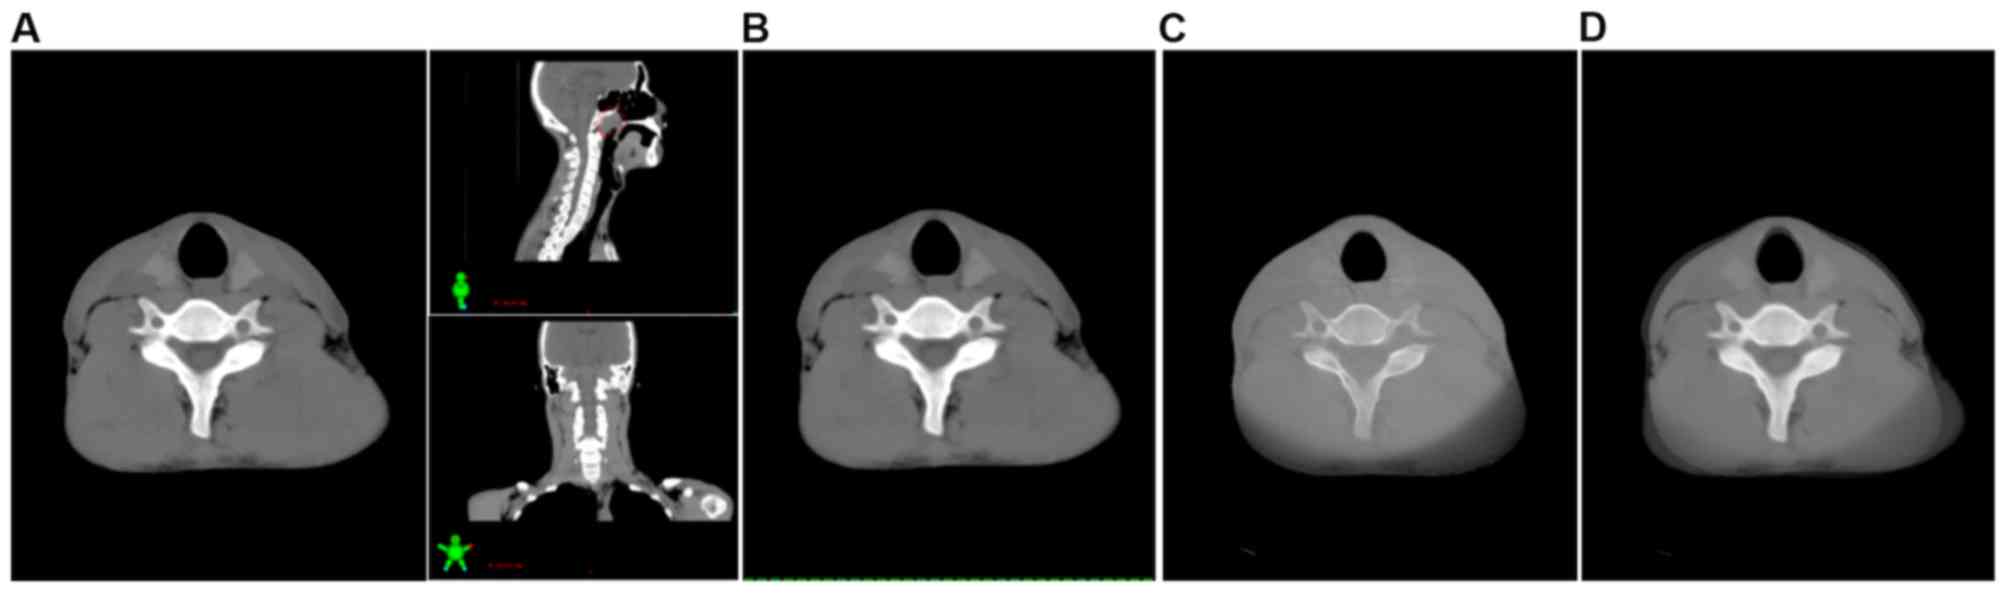

Figure 3.

Image registration in the lower neck region by automatic bone matching and manual fine-tuning. (A) Planning CT images of the cross section, coronal plane and sagittal plane in a patient with NPC; cervical vertebrae 4–6 were used as a bony landmark for automatic bone matching and manual fine-tuning method. (B) Image of the lower neck in planning CT. (C) Image of the lower neck in cone-beam CT. (D) Typical fusion image with planning CT. The involved lymph nodes are outlined in red. CT, computed tomography; NPC, nasopharyngeal carcinoma.